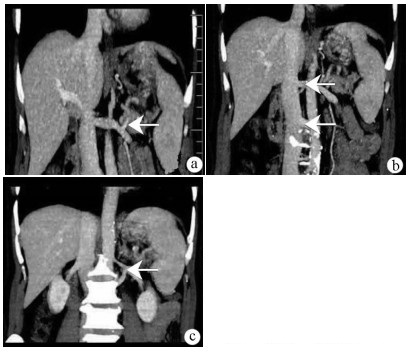

Congenital extrahepatic portosystemic shunt in adults: A report of three cases

Xiaoling ZHAO, Jimin ZHENG, Pingping LI, Yueqin LI

2021, 37(4): 910-913. DOI: 10.3969/j.issn.1001-5256.2021.04.038

Abstract(1367) HTML (606) PDF (2248KB)(67)

Abstract: